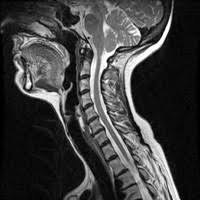

A thorough and accurate cancer diagnosis is the first step in developing a throat cancer treatment plan.at cancer treatment centers of america® (ctca), our experts use a wide range of tools and technologies designed for diagnosing throat cancer and evaluating the disease, with an emphasis on speed to care and timely results. The most common symptom of thyroid cancer is a hard lump on the neck—but most patients experience no symptoms at all. If the cancer cells look like they might have come from the larynx or hypopharynx, an endoscopic exam and biopsy of these areas will be needed. Keep in mind, however, that an ultrasound alone cannot make the diagnosis of cancer. And if this isn't cancer, could anybody offer an explanation as to what would cause a sore throat and growing lump?

Ultrasound is used to see the thyroid gland and the lymph node of the neck. Ultrasounds are not useful for treatment monitoring. Throat cancer most often begins in the flat cells that line the inside of your throat. Connect by text or video with a u.s. An ultrasound may show your doctor if a lump is filled with fluid or if it's solid.

What does thyroid cancer look like on ultrasound.

My 3.8 year old's neck ultrasound shows chain of lymph nodes bilaterally with largest on right 14mm by 6mm and largest on left 13mm by 6mm,the left one is there since a year.few intraparotid largest 5mm.thyroid & both submandibular normal. However, thyroid cancer and most benign nodules can look the same on the ultrasound. Home / uncategorized / what does thyroid cancer look like on ultrasound; If the cancer cells look like they might have come from the larynx or hypopharynx, an endoscopic exam and biopsy of these areas will be needed. What does ovarian cancer look like on ultrasound ? Your voice box sits just below your throat and also is susceptible to throat cancer. Ultrasound imaging can help determine the composition of lump, distinguishing between a cyst and a tumour. What does vulvar cancer look like. Throat cancer most often begins in the flat cells that line the inside of your throat. Needle biopsy is only indicated if there is a mass within the thyroid goiter which is suspicious for malignancy. Doctoroncall is a platform where you can ask more about your health conditions. A primary cancer of the lymphatic system is called lymphoma. An ultrasound is a painless procedure that uses sound waves to generate images of the inside of your body.